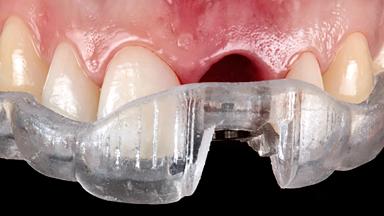

Immediate Implant Placement and Restoration of a Maxillary Left Central Incisor with a Provisional Crown

Leon Pariente and Karim Dada outline the Immediate Implant Placement and Restoration of a Maxillary Left Central Incisor with a Provisional Crown, demonstrating how the hard and soft tissue architecture can be maintained with a Type 1A treatment protocol and a fixed provisional, providing an esthetic and comfortable immediate solution.

A 34-year-old female patient with high esthetic expectations, a non-smoker with no relevant medical history (ASA class 1), was referred to the practice for replacement of her failing maxillary left central incisor (tooth 21), which exhibited a vertical root fracture as diagnosed by the referring endodontist under the microscope. This case illustrates a type 1A treatment protocol (Gallucci and coworkers 2018) complete with diagnosis, treatment decisions, and clinical and laboratory steps.